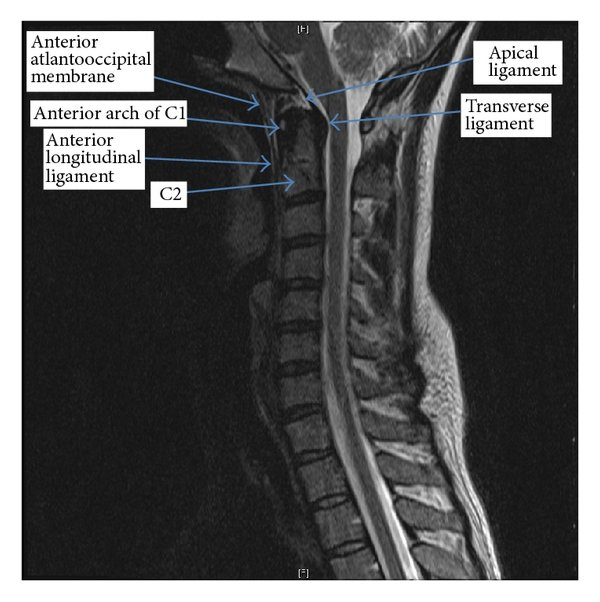

Upper Cervical Injuries Require Specialized Imaging

The upper cervical spine—particularly the relationship between the skull, C1, and C2—is highly specialized and uniquely vulnerable to trauma. These segments rely heavily on ligaments for stability and contain dense neurological structures.

Standard cervical MRI protocols may not adequately visualize:

- Alar ligaments

- Transverse ligament

- Capsular ligaments of the upper cervical joints

This is where proton density (PD) MRI sequences become important.

Why Proton Density (PD) MRI Matters

Proton density MRI is optimized to highlight soft tissue contrast, making it particularly useful for evaluating ligaments and joint capsules.

Upper cervical PD imaging can help identify:

- Ligament thickening or disruption

- Signal changes suggesting sprain or tearing

- Asymmetry between stabilizing structures

- Inflammatory changes related to trauma

For patients with persistent headaches, dizziness, neck instability, or neurological symptoms after a crash, these findings can be clinically significant.